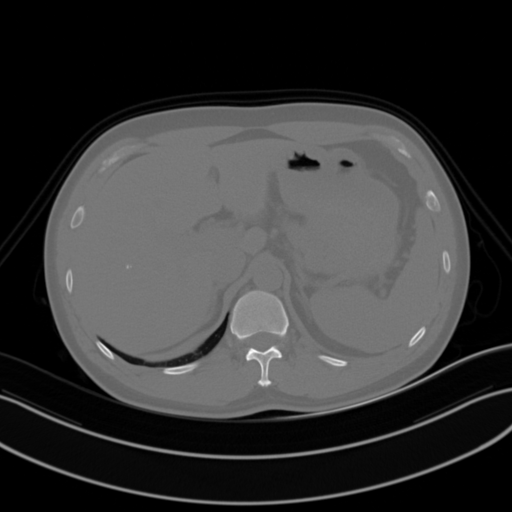

URO dot AI